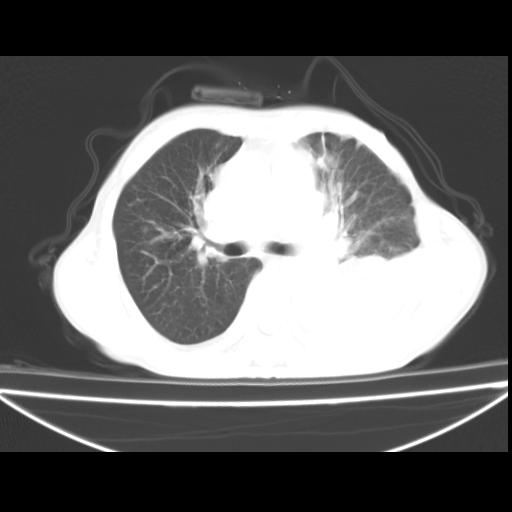

以下是引用随光逐影在2010-3-24 19:15:00的发言:[br]结合病史,考虑双肺及纵隔淋巴结多发转移、左侧胸膜转移并左侧大量胸水,左下肺膨胀不全。

以下是引用zxl51642在2010-3-24 18:49:00的发言:[br]结合乳腺癌术后病史,考虑双肺及纵隔淋巴结多发转移、左侧胸膜转移并左侧大量胸水、左下肺膨胀不全。